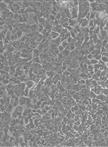

Continue to assess confluency, dissociation requirements, and consolidation as your P1 organoids grow. From this point, the normal and tumor organoids can differ greatly in their needs and must be considered at different time points due to their growth rate (Figure 1).

Figure 1. Patient-derived organoids from normal endometrium and cancerous tissues. A. Organoids from normal endometrium, FIGO1 (low grade), FIGO2 (intermediate grade), FIGO3 (high grade), serous cancer, and carcinosarcoma demonstrating that all histologic subtypes can be cultured and maintained through several passages. B. Serous cancer organoids demonstrating survival and maintenance over several passages in culture at passage 1 (P1), passage 7 (P7), and passage 14(P14). Scale bars: 100 μm (10×) and 200 μm (4×).